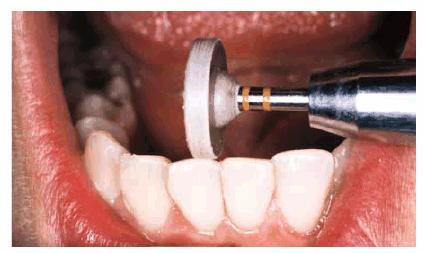

(Figure 24-3C) and mandibular arches (Figure 24-3D). Next, the lateral incisors were

Figure 24-3C: Cosmetic contouring was first performed on the maxillary central incisors and mandibular anterior.

Figure

24-3D: After contouring the mandibular anterior teeth, they were polished with

an impregnated aluminum oxide wheel (Cosmetic Contouring Kit, Shofu,